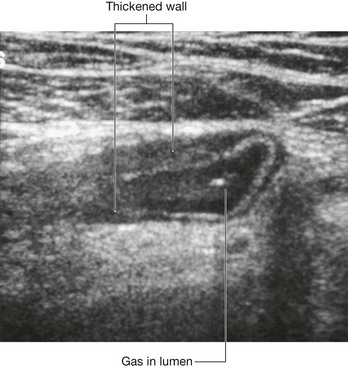

In the clinic

Other approaches use much smaller incisions. With the advent of small cameras and the development of minimal access surgery, tiny incisions can be made in the anterior abdominal wall and cameras inserted. The peritoneal cavity is “inflated” with carbon dioxide to increase the space in which the procedure is performed. Further instruments may be inserted through small portholes, and procedures such as cholecystectomy (removal of the gallbladder) and appendectomy (removal of the appendix) can be carried out, allowing the patient to return home sooner than a large abdominal incision would allow.